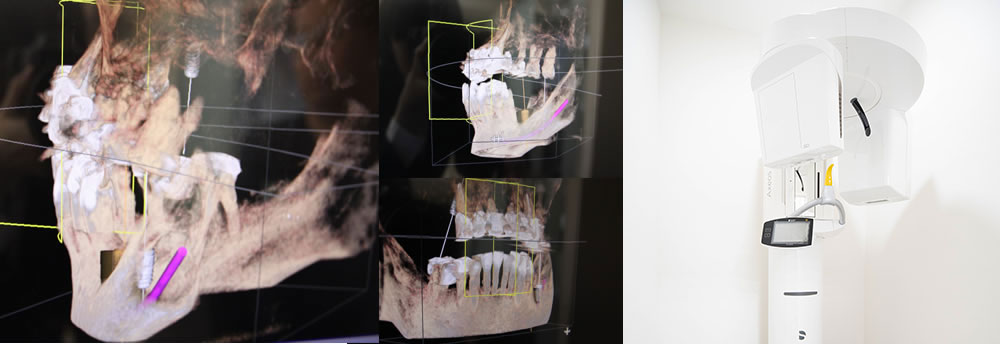

2次元のレントゲンでは確認できない血管や骨と歯の状況、未確認の病巣を確認することができます。外科処置をする際には、必須の検査です。また、3次元のデータ画像を元にインプラント治療のシミュレーション等も可能です。

従来の2D(平面)のレントゲン撮影では、神経・血管の走行位置や骨量(骨の幅・高さ)など顎の内部構造を立体的に見ることはできませんでしたが、歯科用コーンビームCTを使用することで、 3D(立体)の精密な情報を得られます。

それだけでなく、上顎洞(目の下・鼻の横の空洞)の形状や粘膜の状態、病巣の有無なども立体的に把握できます。